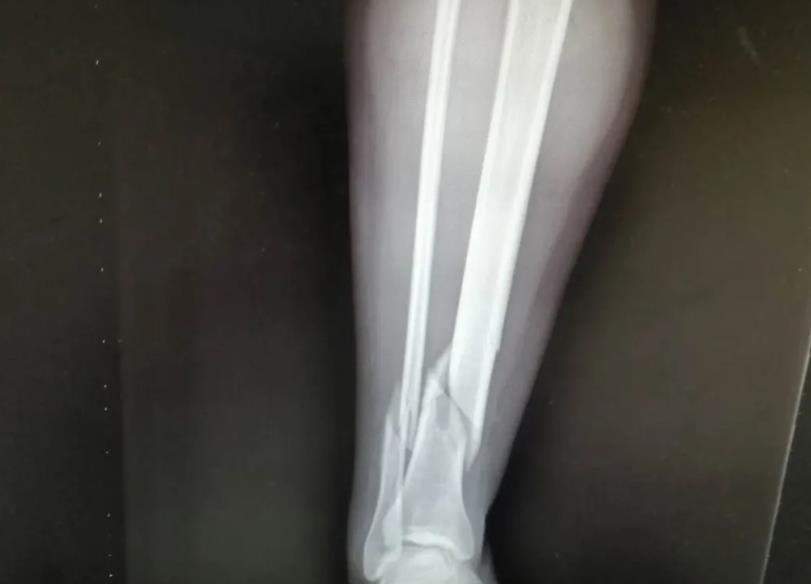

来到医院后,经过门诊检查和摄片后初步诊断为“右胫腓骨粉碎性骨折”,骨科谢业东主任详细的询问病情和经往病史后,首先予以手法牵引复位石膏外固定以减轻患者骨折错位后的疼痛,防止断裂后的骨头尖锐处磨破皮肤后造成感染,打完石膏后杨女士在护士和家属的陪同协助下回到了病房,然后护士对患者用冰敷减轻内出血和水肿,预防血栓形成。住院第二天,医生在例行查房的时候见到杨女士的患肢肿胀,石膏要比前一天紧了一点,于是给她松开后予以重新固定,让病人感到舒适,也能防止患肢因过度包扎导致血流不通畅,造成坏肢。

随后,医生根据杨女士的自身情况对她说明要等到患肢消肿后方可行手术,没消肿做手术的话会对术后伤口愈合不良,但考虑到其患肢自行消肿时间会比较长,所以建议予中药外敷以减轻肿胀和疼痛情况,杨女士表示接受治疗。中药外敷了几天后,效果明显,护士查房的时候问到患者感受,杨女士说第一天就感觉到效果了,明显没有之前那么痛了,于是在患肢消肿后就可以准备做手术了,谢业东主任给患者耐心讲解术前、术中、术后的注意事项以及术后的功能锻炼,杨女士在了解自己的治疗方案后,对手术更有信心了,在完善了术前相关检查后,手术于3月22日上午进行,行右胫腓骨开放复位内固定术,手术过程非常顺利,患者恢复良好,术后在医生护士的指导下进行康复功能锻炼,现已康复出院。